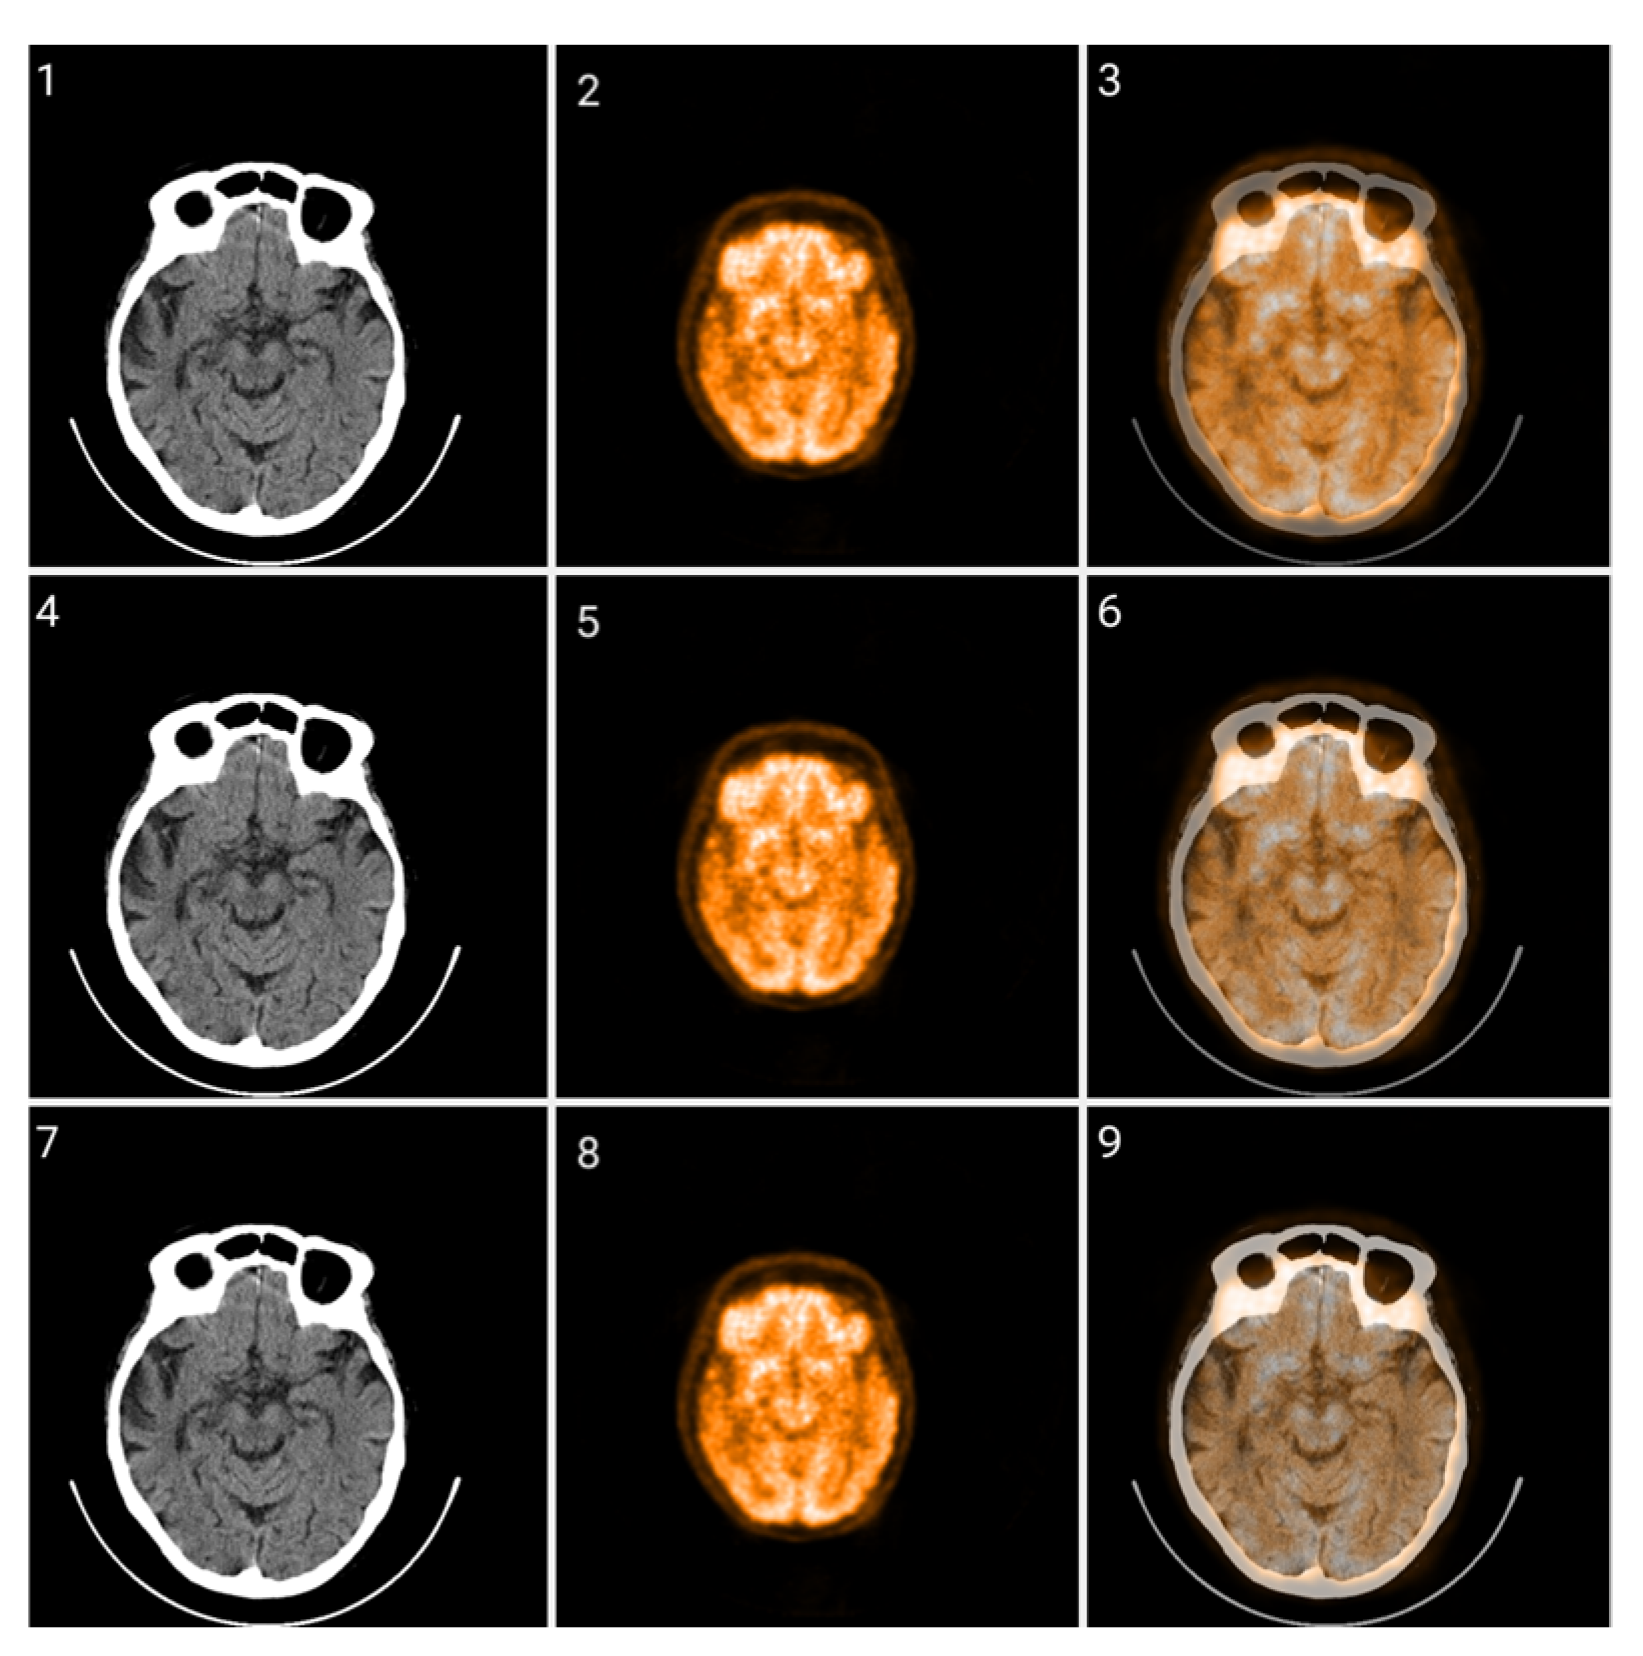

2.2. Method 1: Colormap Information Transform (CIT)

3.1. CIT Application